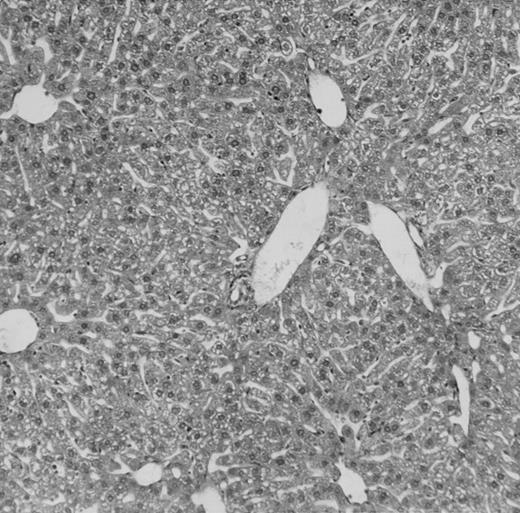

(C) B6 mice receiving FVB BM plus EpΔTK T cells and treated with GCV. (D) B6 mice receiving FVB BM plus EpΔTK T cells, treated with GCV, and developing a late onset GVHD (day 54).

Protection from GVHD was slightly less efficient in the group receiving EpΔTK CD3+ T cells. The survival rate was 79% at day 60 and 67% at day 120 (Fig 2B). However, two different outcomes must be distinguished. On the one hand, a majority of mice behaved as GCV-treated animals receiving EpTK T cells. They were apparently healthy, presented no skin lesions during a 120-day observation period, and showed complete donor-type hematologic reconstitution. There were no histological signs of GVHD in the spleen or liver (Fig 4C).